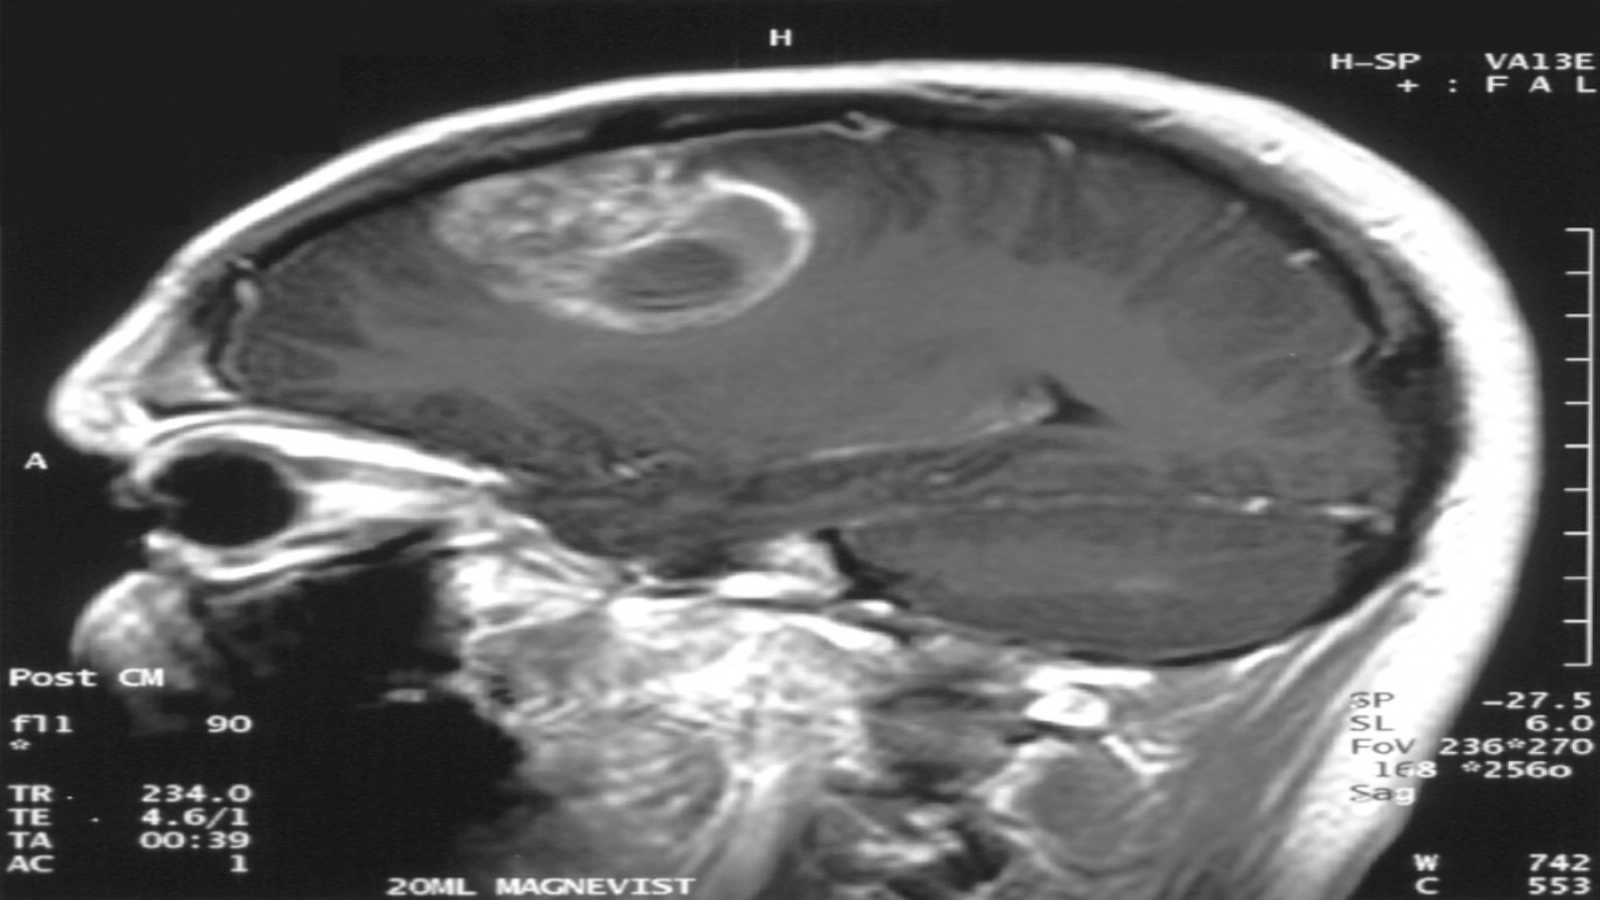

O echipă din Israel a descoperit o metodă prin care să distrugă tumorile glioblastomului și a obținut rezultate remarcabile pe modelele animale și liniile celulare umane. Nouă metodă folosită pentru a eradica tumorile cerebrale mortale „înfometează” tumorile eliminând sursa lor de energie, potrivit 360medical.ro.

Într-un studiu considerat revoluționar, cercetătorii de la universitatea din Tel Aviv au eliminat în mod eficient glioblastomul, un tip extrem de letal de cancer cerebral.